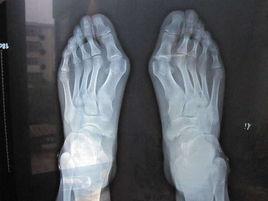

拇外翻常呈對稱性,拇趾的跖趾關節輕度半脫位,內側關節囊附著處因有牽拉,可有骨贅形成,第1跖骨頭的突出部分,因長期受鞋幫的摩擦局部皮膚增厚,並可在該處皮下產生滑囊,如紅腫發炎,則成為拇滑囊炎,嚴重者拇趾的跖趾關節可產生骨關節炎,引起疼痛。第二,三跖骨頭跖麵皮膚因負擔加重,形成胼胝.第二趾近側趾骨間關節處背側皮膚因與鞋幫摩擦可形成胼胝或雞眼.

主要表現為腳部畸形和疼痛。其畸形表現為腳拇趾外翻,向其它腳趾方向偏斜,而腳拇指根部的跖骨頭明顯突出。畸形嚴重時,趾骨頭突出處可呈半球形,第二腳趾也因為擠壓而向腳背面突出。大多數畸形嚴重的患者,都會出現不同程度的疼痛。疼痛主要是因為跖骨頭的突出部分,長期受鞋幫的擠壓、摩擦,使得局部皮膚增厚、骨質增生,並可在該處皮下產生滑囊、滑囊炎,引起紅腫、疼痛。